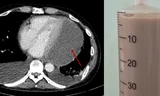

![]() |

| Bệnh nhân ung thư đang được vào thuốc hóa trị tại khoa Hóa trị Bệnh viện Chợ Rẫy |